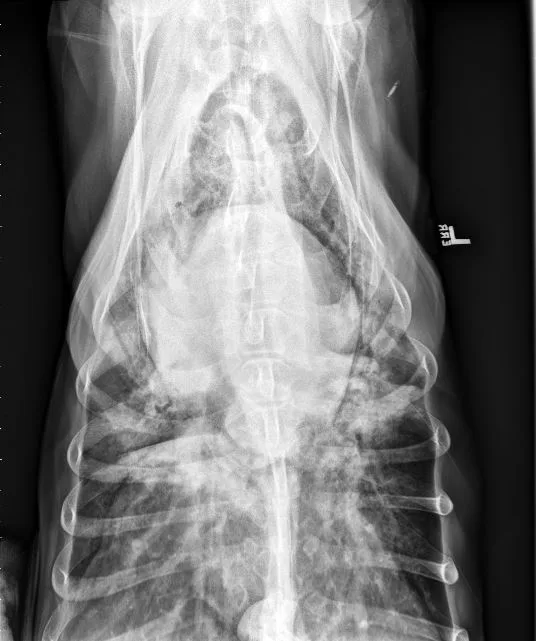

A subset of patients with acquired heart disease may develop left-sided congestive heart failure (CHF). In addition to left-sided cardiomegaly, dogs with active CHF secondary to MMVD commonly exhibit lobar pulmonary venous enlargement on radiographs, as well as an interstitial to alveolar radiographic lung pattern that typically develops in the perihilar region and right caudal lung lobes (Figure 8); however, in dogs with DCM, this lung pattern may be seen in the ventral lung lobes (Figure 9). The radiology lung score is an objective method to quantify severity but was not associated with the recurrence of CHF or survival in one study.16 Dogs administered diuretics may not have pulmonary venous dilation, and some dogs with CHF secondary to acute increase in left atrial pressure (eg, aortic valve endocarditis, chordae tendineae rupture) may not have significant cardiomegaly.

FIGURE 8 DV (left) and left lateral (right) projections consistent with left-sided CHF in a dog with advanced MMVD. Pulmonary venous distention (arrowheads), an interstitial to alveolar pattern in the perihilar region extending caudodorsally, cardiomegaly, and aerophagia are present. VHS, VLAS, M-VLAS, and VRHi collected from the left lateral view are 10.9, 2.8, 4.8, and 3.2, respectively.